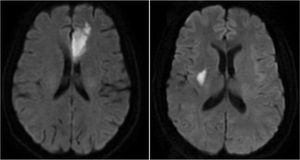

All images were assessed by two radiologists blind to the clinical information. The discrepancy was resolved by a visual consensus. The diagnosis of ischemic stroke was based on the acute neurological symptoms and the visible infarcts on MRI with hyperintense on DWI (Fig. 1). Lacunar stroke was defined as single or multiple acute ischemic infarcts in the perforating-artery territories or subcortical regions, with the longest diameter less than 20 mm on DWI,1920 otherwise the patients were deemed to have a non-lacunar stroke. According to the specific diagnosis, patients were assigned to either lacunar stroke group or the non-lacunar stroke group.

The acute infarctions of two patients of PSD on DWI. Left: A 63-year-old female, she was admitted because of right limb weakness and aphagia with NIHSS score 3. The brain MRI showed acute infarction in left frontal lobe. After hospitalization for 7 days, she was discharged with a NIHSS score 2. Three months later she had no obvious functional impairment but had a GDS score 9 and was identified to have PSD. Right: A 54-year-old male, he was admitted because of weakness and numbness of left limb with NIHSS score 3. The brain MRI showed acute lacunar infarction in right basal ganglia. During hospitalization he didn't react well to the treatment and had neurological deterioration with NIHSS score 5 at the 7th day of hospitalization. Three months later he had a GDS score 10 and was identified to have PSD.